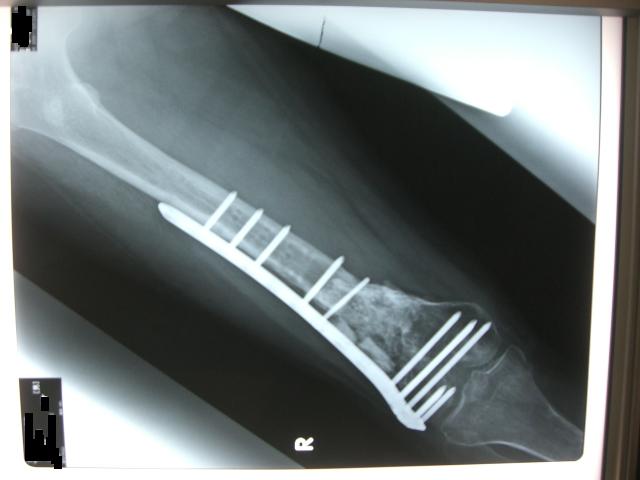

右足の手術を何時やるのか、そろそろ決めたい所だけど

今月の骨順調に骨の強度は上がってきてます。

もう何時手術しても良い状態だそうですが・・・